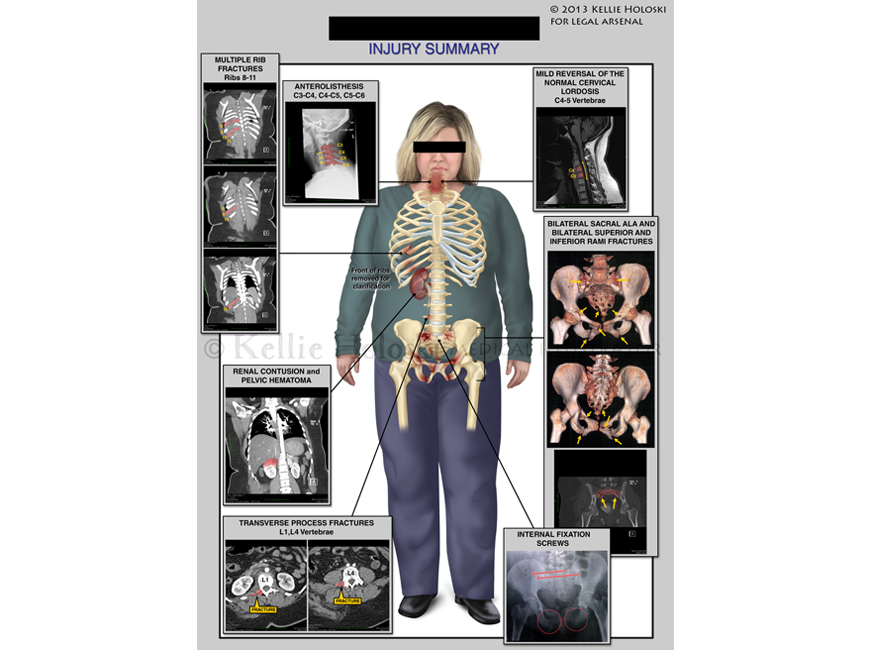

Injury Summary,

Adobe Photoshop

Courtroom exhibit;

©Kellie Holoski